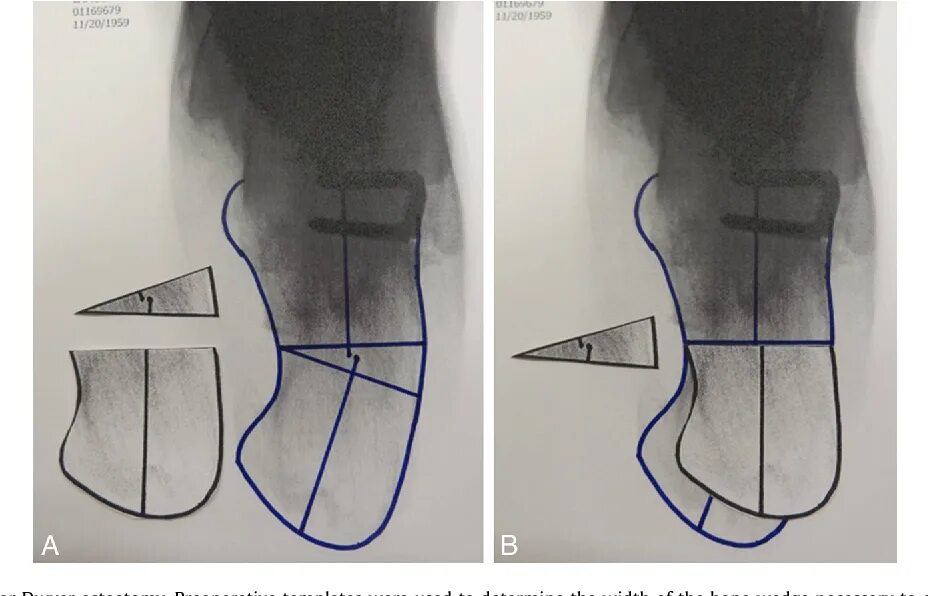

Пяточная остеотомия